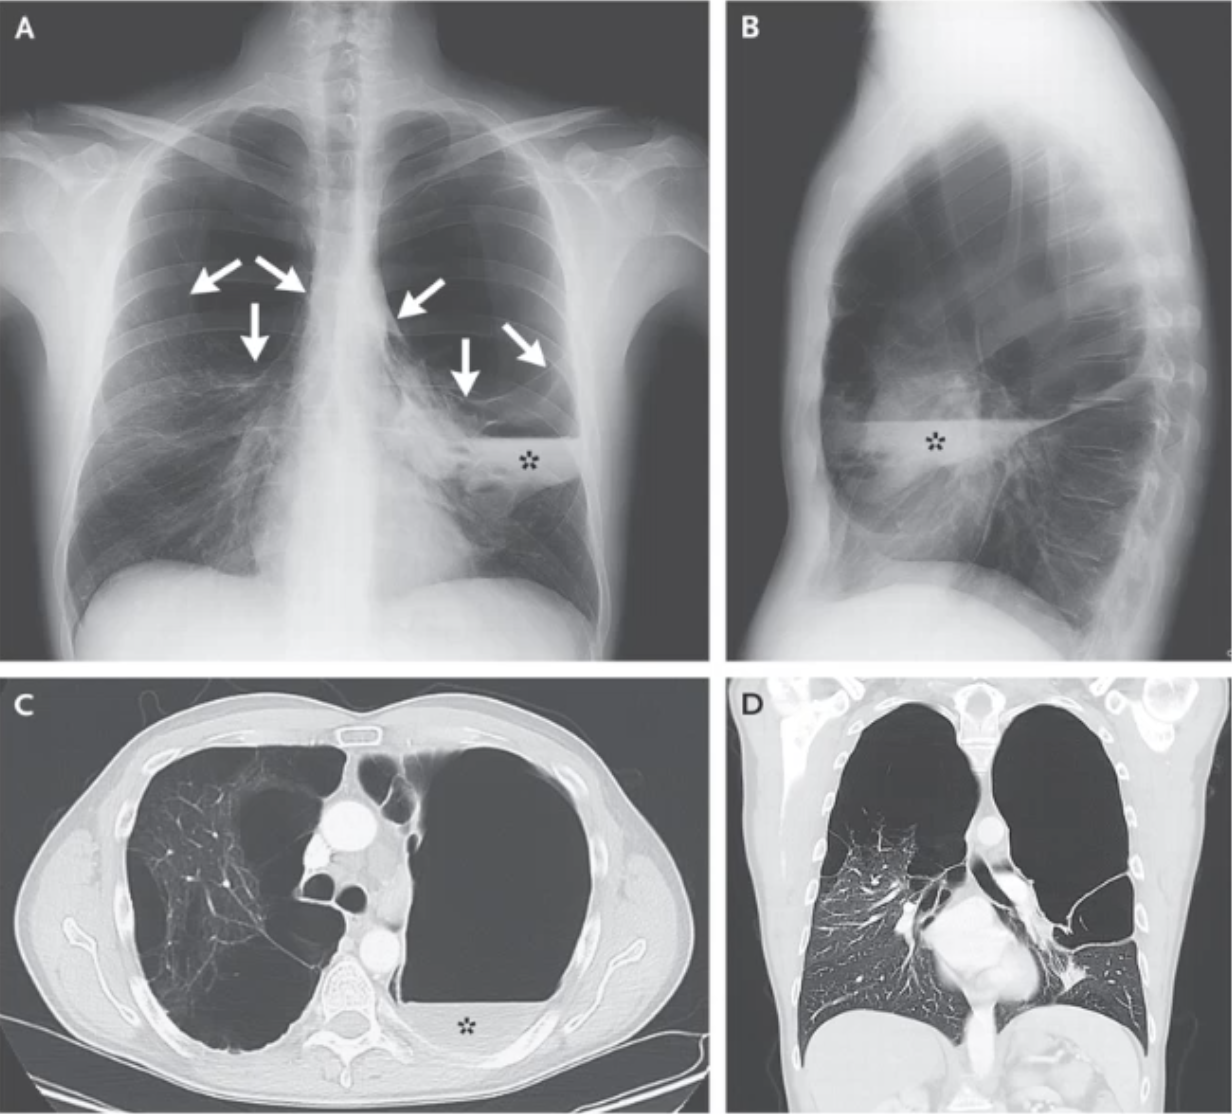

What do these scans show?

Contrast enhanced scans show the location of a pulmonary embolism.

Oligaemia where vessels have collapsed distal to the clot.

What would typically be seen in the history and examination of a patient with COPD-linked Bullous Disease?

Lack of lung markings and fluid-air levels on CXR/CT

Decreased breath sounds, hyper-resonant percussion notes.

History of COPD/Smoking.